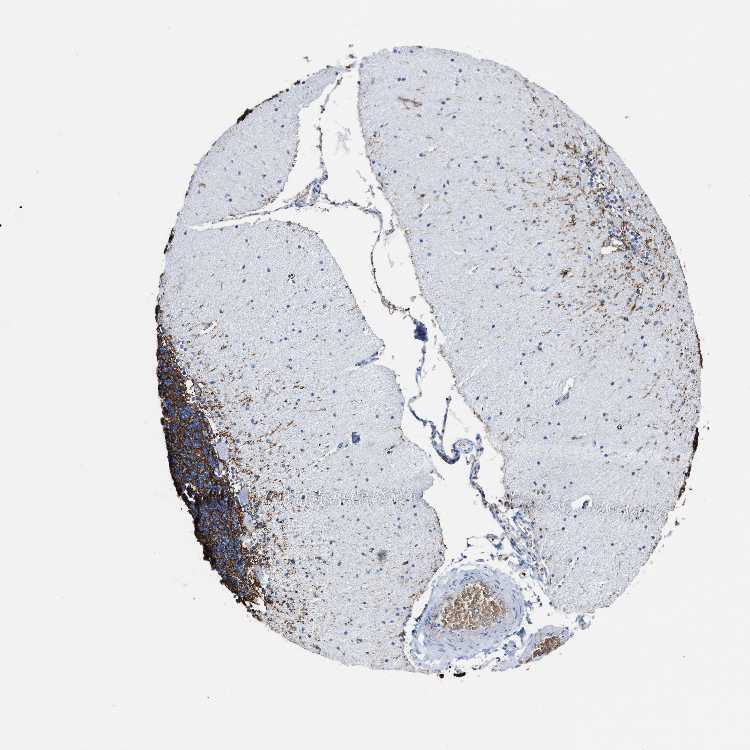

CEREBELLUM - Antibody stainingi

Antibody staining in the annotated cell types in the current human tissue is reported as not detected, low, medium, or high, based on conventional immunohistochemistry profiling in selected tissues. This score is based on the combination of the staining intensity and fraction of stained cells.

Each image is clickable and will lead to virtual microscopy that enables deeper exploration of all samples and also displays staining intensity scores, fraction scores and subcellular localization as well as patient and tissue information for each sample.

Antibody HPA019206Antibody CAB001707

Purkinje cells Not detectedNot detected

Cells in granular layer HighNot detected

Cells in molecular layer Not detectedNot detected